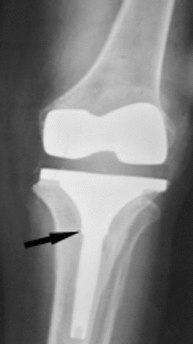

Today, total knee arthroplasty (TKA) is one the most commonly performed surgeries worldwide. The purpose of this article is to review the appearance of normal post-TKA roentgenographs and describe the correct sequence for their interpretation. It is unwise to depend solely on patients' symptoms when diagnosing TKA complications because serial radiographs can foresee failures well before they manifest clinically. Ideal post-TKA radiographs comprise whole lower extremity anteroposterior and lateral views taken under weight bearing conditions along with a skyline view of the patellofemoral joint. Among other things, weight bearing exposes the true alignment, ligamentous laxity and polyethylene wear. On the basis of follow-up of our TKA cases, we have drawn up a protocol for assessing postoperative X-ray films after TKAs. Following the proposed sequence, surgeon can easily decide how to proceed with follow-up and foresee complications. Careful interpretation of postoperative radiographs after TKA is essential to careful monitoring of patients and implant survival.